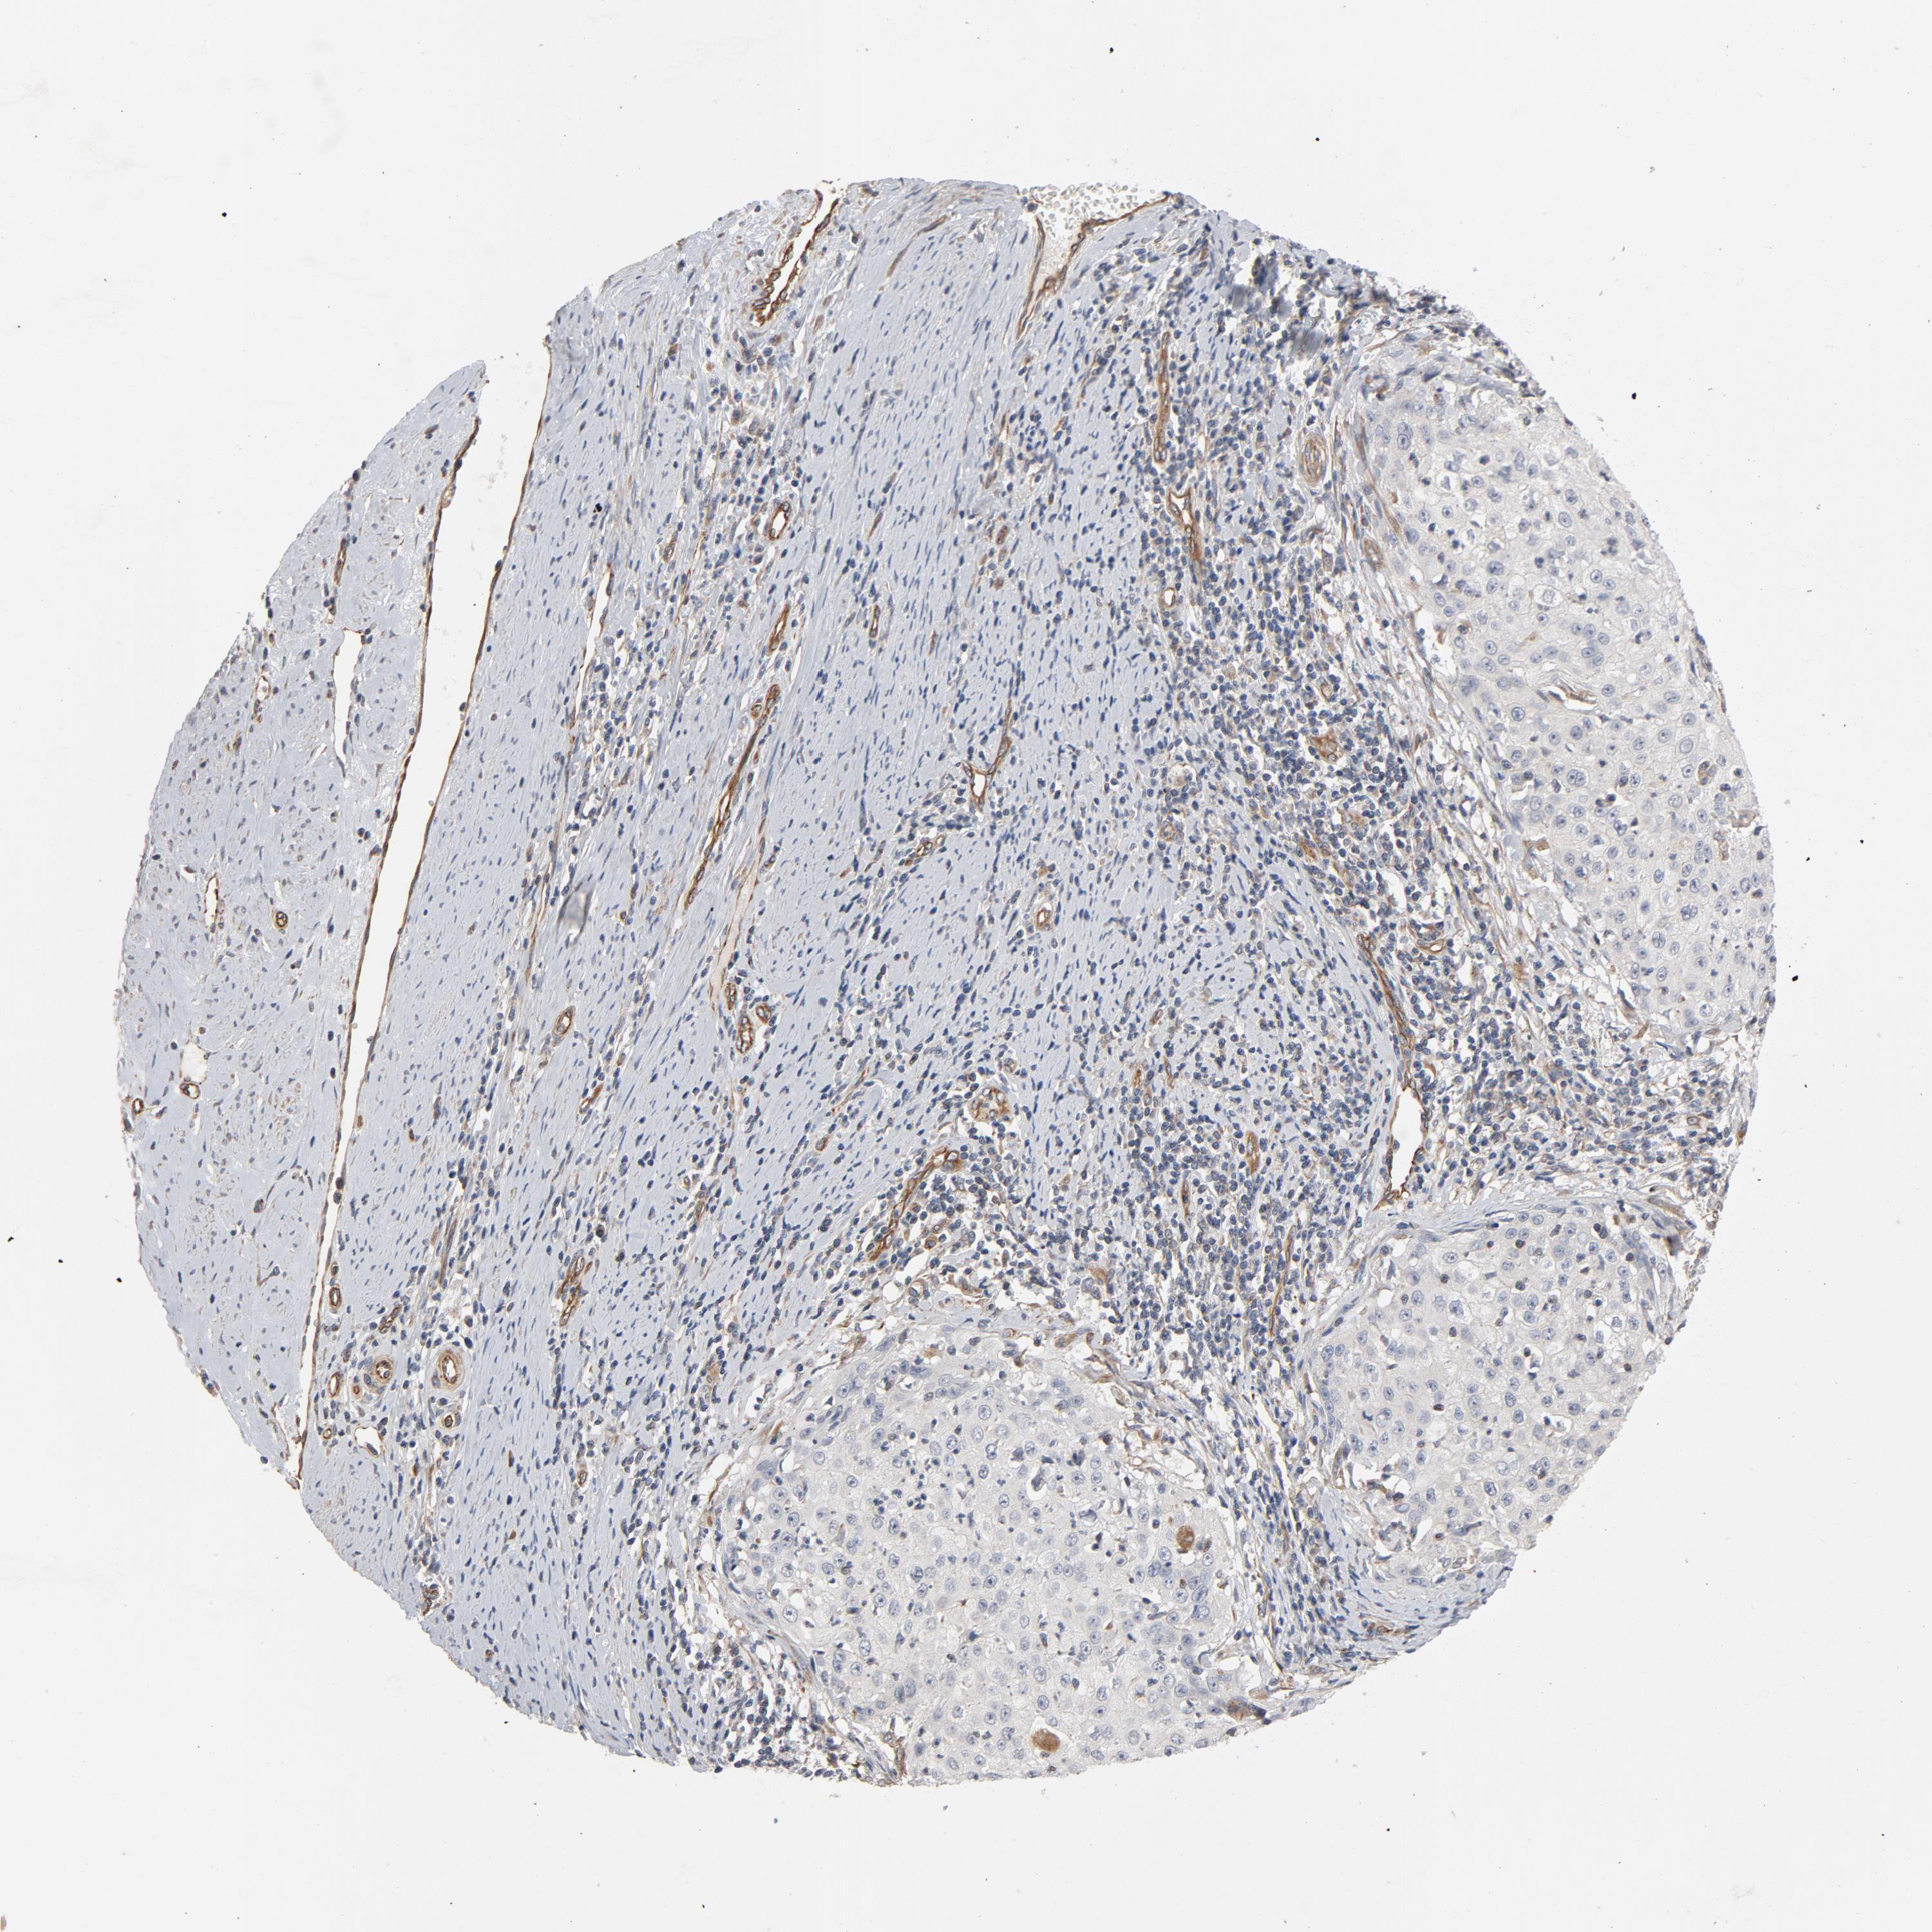

CERVICAL CANCER - Protein expressioni

A mouse-over function shows sample information and annotation data. Click on an image to view it in a full screen mode. Samples can be filtered based on level of antibody staining by selecting one or several of the following categories: high, medium, low and not detected. The assay and annotation is described here.

Note that samples used for immunohistochemistry by the Human Protein Atlas do not correspond to samples in the TCGA dataset.

Antibody stainingi

Antibody staining in the annotated cell types in the current human tissue is reported as not detected, low, medium, or high, based on conventional immunohistochemistry profiling in selected tissues. This score is based on the combination of the staining intensity and fraction of stained cells.

Each image is clickable and will lead to virtual microscopy that enables deeper exploration of all samples and also displays staining intensity scores, fraction scores and subcellular localization as well as patient and tissue information for each sample.

Antibody HPA003747

Antibody HPA019769

Squamous cell carcinoma, NOS